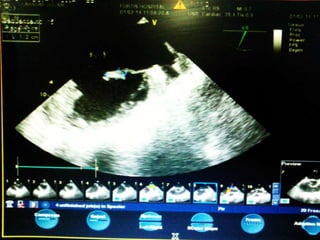

• Trans Esophageal Echocardiography done on

1ST Feb showed Mitral valve Vegetation

measuring 1.2 x 0.7 cm attached to AML, Flail

AML, non coapting leaflets with severe MR,

Aortic vlve – tri leaflets , No AR, pulmonary

valve normal, no PR, Tricuspid valve- mild TR,

Left Atrium mildly dilated , no LA appendage

clot.